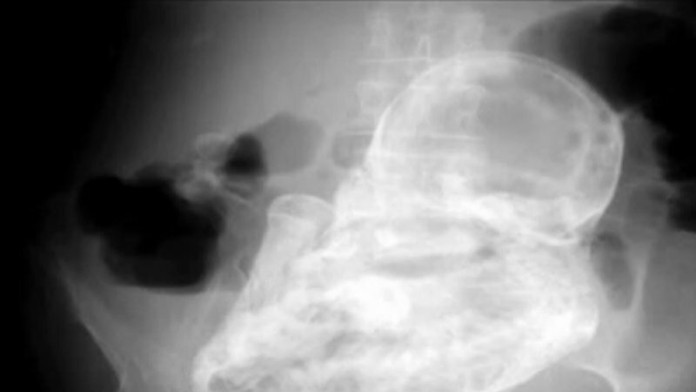

S naozaj nezvyčajným prípadom sa stretli lekári v kolumbijskej nemocnici v Bogote. Na pohotovosť prišla 82-ročná dôchodkyňa s bolesťami brucha. Odborníci si najskôr mysleli, že sú to žlčové kamene, ale skutočná príčina bolesti ich šokovala.

Lekár, ktorý ženu vyšetroval, si všimol v jej brušnej dutine niečo neobvyklé. Pacientke urobili ultrazvuk, ktorý ale nič neodhalil.

Röntgenové vyšetrenie ukázalo pravého vinníka. Lekári sa ale domnievali, že ide o nádor. Neskôr zistili, že to bol kalcifikovaný plod dieťaťa.

Takýto jav nastane vtedy, keď v tele ženy zahynie plod dieťaťa počas mimomaternicového tehotenstva. Označuje sa ako lithopedion alebo „skamenené dieťa".

Plod sa v tele dôchodkyňa nachádzal 40 rokov. Pacientku museli previesť do inej nemocnice, kde podstúpi operáciu, pri ktorej jej plod z tela odstránia.